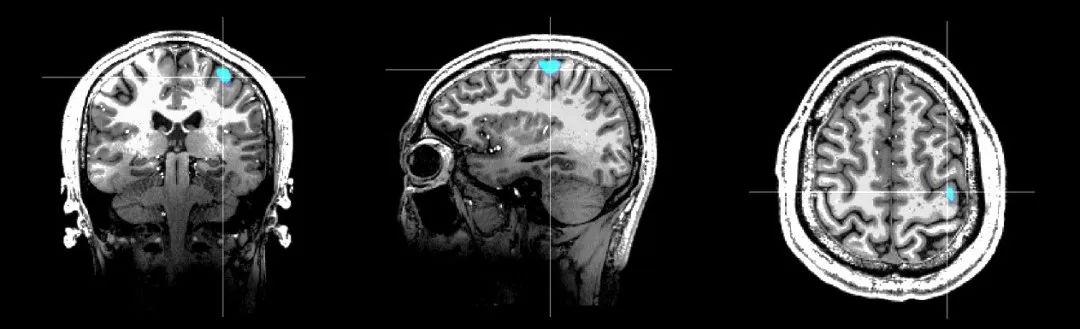

Marvel MEG?ÎÞÒºº¤ÄÔ´ÅͼÒÇÊÇ»ùÓÚÍêÈ«×ÔÖ÷֪ʶ²úȨµÄÐÂÐÍÉúÎKÈõ´Å³¡Ì½²âÊÖÒÕ¡ª¡ªÔ­×Ó´ÅÁ¦¼ÆÑз¢¶ø³É£¬£¬£¬£¬£¬¶ÔÄÔ²¿´Å³¡µÄ̽²âѸËٶȵִïÁË10fT¨C 15fT£¨1fT = 10-15Tesla£¬£¬£¬£¬£¬µØÇò´Å³¡µÄÊ®ÒÚ·ÖÖ®Ò»£©¡£¡£¡£¡£¡£¡£Marvel MEG?ÎÞÒºº¤ÄÔ´ÅͼÒÇÒÔ·ÇÇÖÈë·½·¨¼ì²âºÍÏÔʾ´óÄÔÉñ¾­×éÖ¯·ÅµçÔ˶¯±¬·¢µÄ´Å³¡ÐźÅ£¬£¬£¬£¬£¬¾ÙÐÐÄÔ¹¦Ð§³ÉÏñºÍ¾«×¼¶¨Î»¡£¡£¡£¡£¡£¡£¸Ã²úÆ·¼æ±¸ºÁÃë¼¶µÄʱ¼äÇø·ÖÂʺͺÁÃ×¼¶µÄ¿Õ¼äÇø·ÖÂÊ£¬£¬£¬£¬£¬Í¬Ê±ÎÞ´´¡¢ÎÞ·øÉä¡¢ÎÞÐèÔìÓ°¼Á£¬£¬£¬£¬£¬²¢¼¯³É¸ß¾«¶È´Å³¡¿ØÖÆÏµÍ³ºÍ¶àģ̬´Ì¼¤ÏµÍ³£¬£¬£¬£¬£¬¿ÉΪÉñ¾­ÏµÍ³¼²²¡µÄ¿ÆÑ§Ñо¿ºÍÁÙ´²Ó¦ÓÃÌṩÎÞ´´¡¢¾«×¼Õï¶ÏµÄÊֶΡ£¡£¡£¡£¡£¡£ÕâÒ»¹ú²ú¸ß¿Æ¼¼×°±¸ÔçǰÒÑ»ñÅú±±¾©ÊÐÁ¢ÒìÒ½ÁÆÆ÷е£¬£¬£¬£¬£¬²¢ÔÚ±±¾©Ìì̳ҽԺ¾ÙÐÐ×¢²áÁÙ´²Ñо¿¡£¡£¡£¡£¡£¡£Í¨¹ý±ÈÕÕÑо¿·¢Ã÷£¬£¬£¬£¬£¬Marvel MEG?ÎÞÒºº¤ÄÔ´ÅͼÒÇʹ³£ÎÂÏÂʵÏÖ³¬¸ßѸËٶȵĴų¡Ì½²â³ÉΪ¿ÉÄÜ£¬£¬£¬£¬£¬¿É½â¾ö¹Å°å³¬µ¼SQUIDÄÔ´ÅͼµÄÍ´µã£¬£¬£¬£¬£¬¾ß±¸³£ÎÂÊÂÇé¡¢ÎÞÐèÒºº¤£¬£¬£¬£¬£¬ÎÞÐ轨Éèµ¥¶ÀµÄ´ÅÆÁÕÏ·¿£¬£¬£¬£¬£¬¼ì²âЧÂÊ¸ßµÈÆæÒìÓÅÊÆ£¬£¬£¬£¬£¬´ó´óÌáÉýÁËÁ¢Òì²úÆ·µÄ¿É¼°ÐÔ¡£¡£¡£¡£¡£¡£

¿µ½¡ÈËÓÒÊÖÔ˶¯¹¦Ð§ÇøÓë7.0TºË´ÅÓ°ÏñÈÚºÏЧ¹û